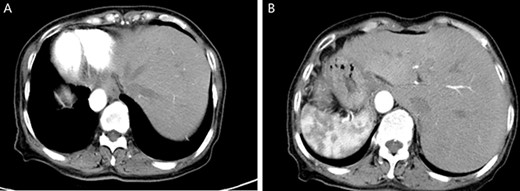

A physical examination revealed that the abdomen is flat, without gastrointestinal type and peristaltic wave, and the right lower abdomen has mild tenderness, with no rebound pain and muscle tension, and the mass can not be touched. Serum tumor markers were not elevated (CEA 2.3 ng/ml and CA-199 4.15 ng/ml). The laboratory examination confirmed mild anemia and hypoproteinemia. Abdominal computerized tomography (CT) showed the apex of the heart on the right side, the liver on the left side of the abdominal cavity (Fig. 1A), the stomach and spleen on the right side of the abdominal cavity (Fig. 1B), confirming SIT. In addition, the chest X-ray confirmed the apex of the heart on the right chest (Fig. 2A), and abdominal CT indicated that the tumor (stage T4N0M0) was located in the descending colon (Fig. 2B).

Chest X-ray showed that the heart was on the right side of the chest (A). Enhanced CT of the lower abdomen showed thickening of the descending colon with stenosis and enhancement, which suggested that it might be a tumor of the descending colon (B, yellow arrow).